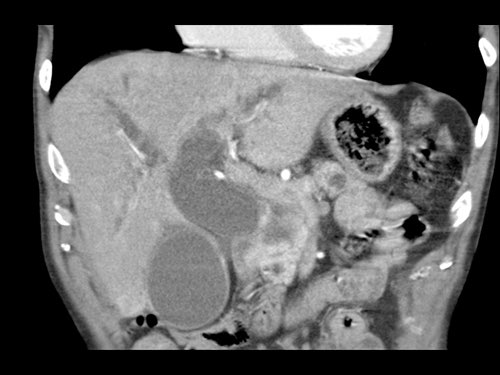

Tái tạo mặt phẳng coronal cho thấy một khối u lớn xuất phát từ cổ tụy với kiểu phát triển xâm lấn (hình A và B).

Có hiện tượng bao quanh động mạch thân tạng 360º (mũi tên trong A).

CT axial MIP tại mức động mạch thân tạng cho thấy hẹp động mạch gan chung bị bao quanh (mũi tên), rất nghi ngờ xâm lấn.